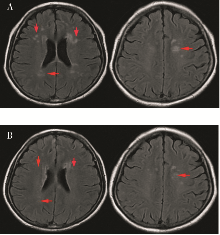

神经精神狼疮是系统性红斑狼疮严重并发症,尤其是累及中枢神经系统时,死亡率明显增加,且目前尚无标准治疗方案。本文报道1例以精神行为异常、谵语为主要表现的神经精神狼疮患者,予以利妥昔单抗序贯贝利木单抗治疗后患者症状缓解,实验室及影像学指标明显改善,为神经精神狼疮的治疗提供了新策略。